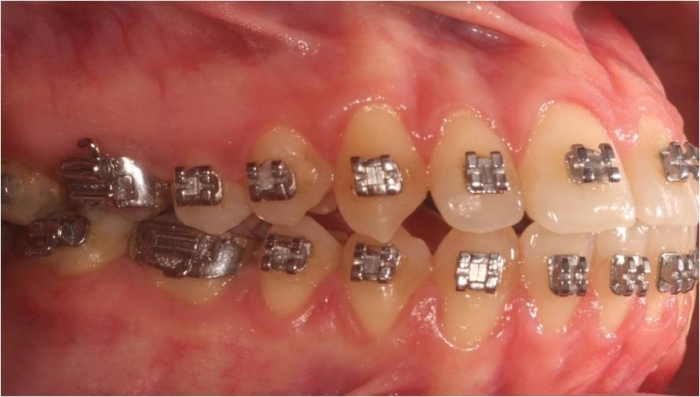

Mordida inicial

Mordida após a cirurgia